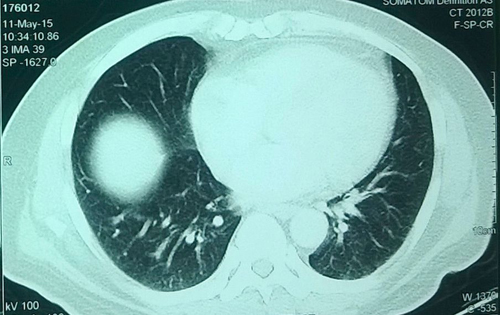

Kết quả chụp X-quang khối u thận của ông Kapleshwar Lal Das. Ảnh: Barcroft

Sau khi kiểm tra, các bác sĩ phát hiện ra một khối u nặng 5,018 kg, tương đương kích cỡ một quả dưa hấu lớn, trong thận của bệnh nhân này. Ông Kapleshwar lập tức được đưa vào phòng phẫu thuật để cắt bỏ khối u khổng lồ.

Ca mổ kéo dài 5 giờ và các bác sĩ khẳng định đây chắc chắn là khối u thận lớn nhất thế giới từ trước tới nay.

Tiến sĩ Mukur Dipi Ray, người chịu trách nhiệm chính của ca phẫu thuật, cho biết: "Chúng tôi đã tiến hành mổ phanh bụng bệnh nhân để cắt bỏ khối u khổng lồ ra khỏi cơ thể. Nó nặng gấp nhiều lần một khối u thông thường, bám chặt vào gan và đại tràng".